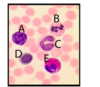

The peripheral blood cell that is most involved in the defence against viral pathogens is indicated by which letter?

A

B

C

D

E

The peripheral blood cell that is most involved in the defence against viral pathogens is indicated by which letter?

A

B

C

D

E